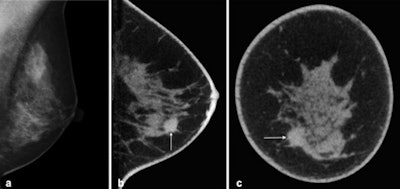

Cone-beam breast CT, noncontrast-enhanced examination. Invasive ductal breast carcinoma is shown on the left. A: Digital mammography on the left in mediolateral oblique (MLO) projection. B: Breast CT, sagittal single slice with depiction of breast carcinoma (arrow) in the caudal breast sections."The Norwegian screening program already showed that when this method is used in combination with mammography, the tumor detection rate can be increased," Wienbeck noted.